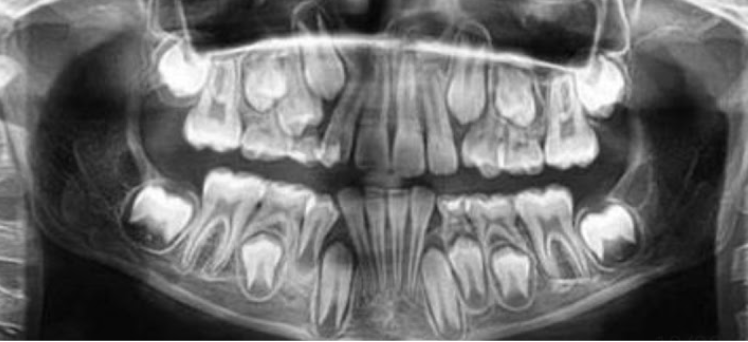

1.Ad. LOWER central incisors present? Yes. definitely 6-7 or older

1. Ad. UPPER CI present? Yes def. 7-8 y.o

3.Ad. Upper LAT incisor present (baby sheds 7-8)? NO so still under 7-8

Conc: pt is under 7